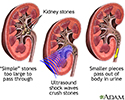

Lithotripsy procedure - illustration

Lithotripsy procedure

illustration

Extracorporeal shock wave lithotripsy (ESWL) is the most common type of lithotripsy. "Extracorporeal" means outside the body.

High-energy shock waves, also called sound waves, guided by x-ray or ultrasound, will pass through your body until they hit the kidney stones. If you are awake, you may feel a tapping feeling when this starts. The waves break the stones into tiny pieces.